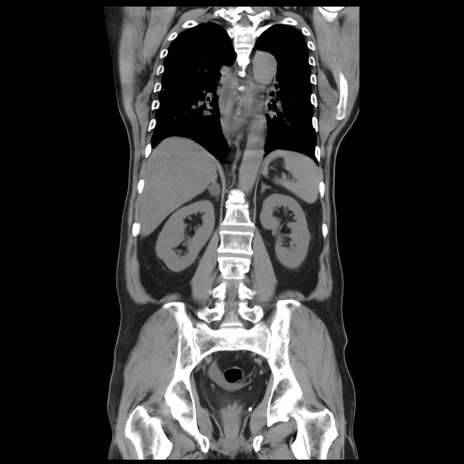

症例20(冠状断像)

【症例】 60歳代男性

【主訴】 腹部膨満、嘔吐

【現病歴】5日前頃より倦怠感を認め食事量減少し4日前の朝嘔吐、食事摂取困難となった。 3日前近医受診し点滴施行され整腸剤などを処方された。 当日他院を受診し、腹部膨満著明、炎症反応の上昇(CRP10.8、WBC11200)あり、紹介受診となる。

【身体所見】 意識JCS1 受け答えがはっきりしないBP 111/57mHg、 P 67bpm、、BT35.2°C、SpO2 97%(RA)、 腹部:膨隆、打診で鼓音あり、全体的に圧痛有り、腸蠕動音(-)、反跳痛ははっきりせず。

【データ】WBC 11400、CRP 14.20